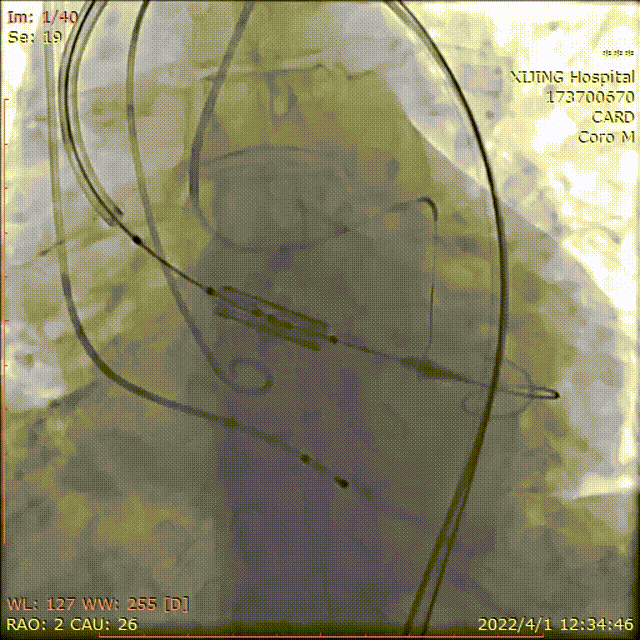

术中DSA影像:

术前造影并测压,显示AS+AR

左冠预埋球囊行冠脉保护

术前主动脉瓣上血压149/47(81),左心室血压199/25(83),最大跨瓣压差50mmHg

25mm球囊预扩张,有腰征,无漏

应用可调完系统顺利过弓

左右窦重合角度造影定位

右窦居中角度造影定位

多角度透视影像下显示可调弯输送器系统能保障瓣膜释放时与主动脉根部的同轴性。

释放26mmPrizValve,瓣架有腰征

术后造影微量PVL,瓣架形态位置理想

术后主动脉瓣上血压174/64(101),左心室血压187/22(77),最大跨瓣压差13mmHg。考虑球囊后扩张对左冠有影响,撤出左冠内球囊,手术结束。